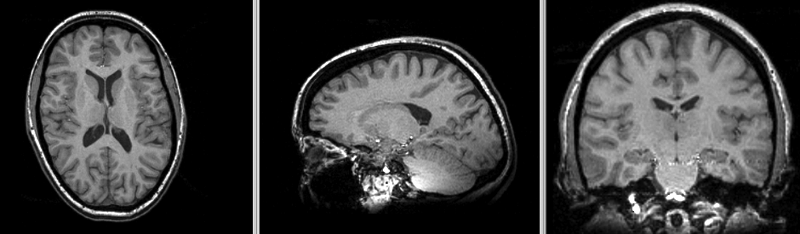

File:RegLib C19 AGif BSplDef.gif

RegLib_C19_AGif_BSplDef.gif (800 × 234 pixels, file size: 264 KB, MIME type: image/gif)